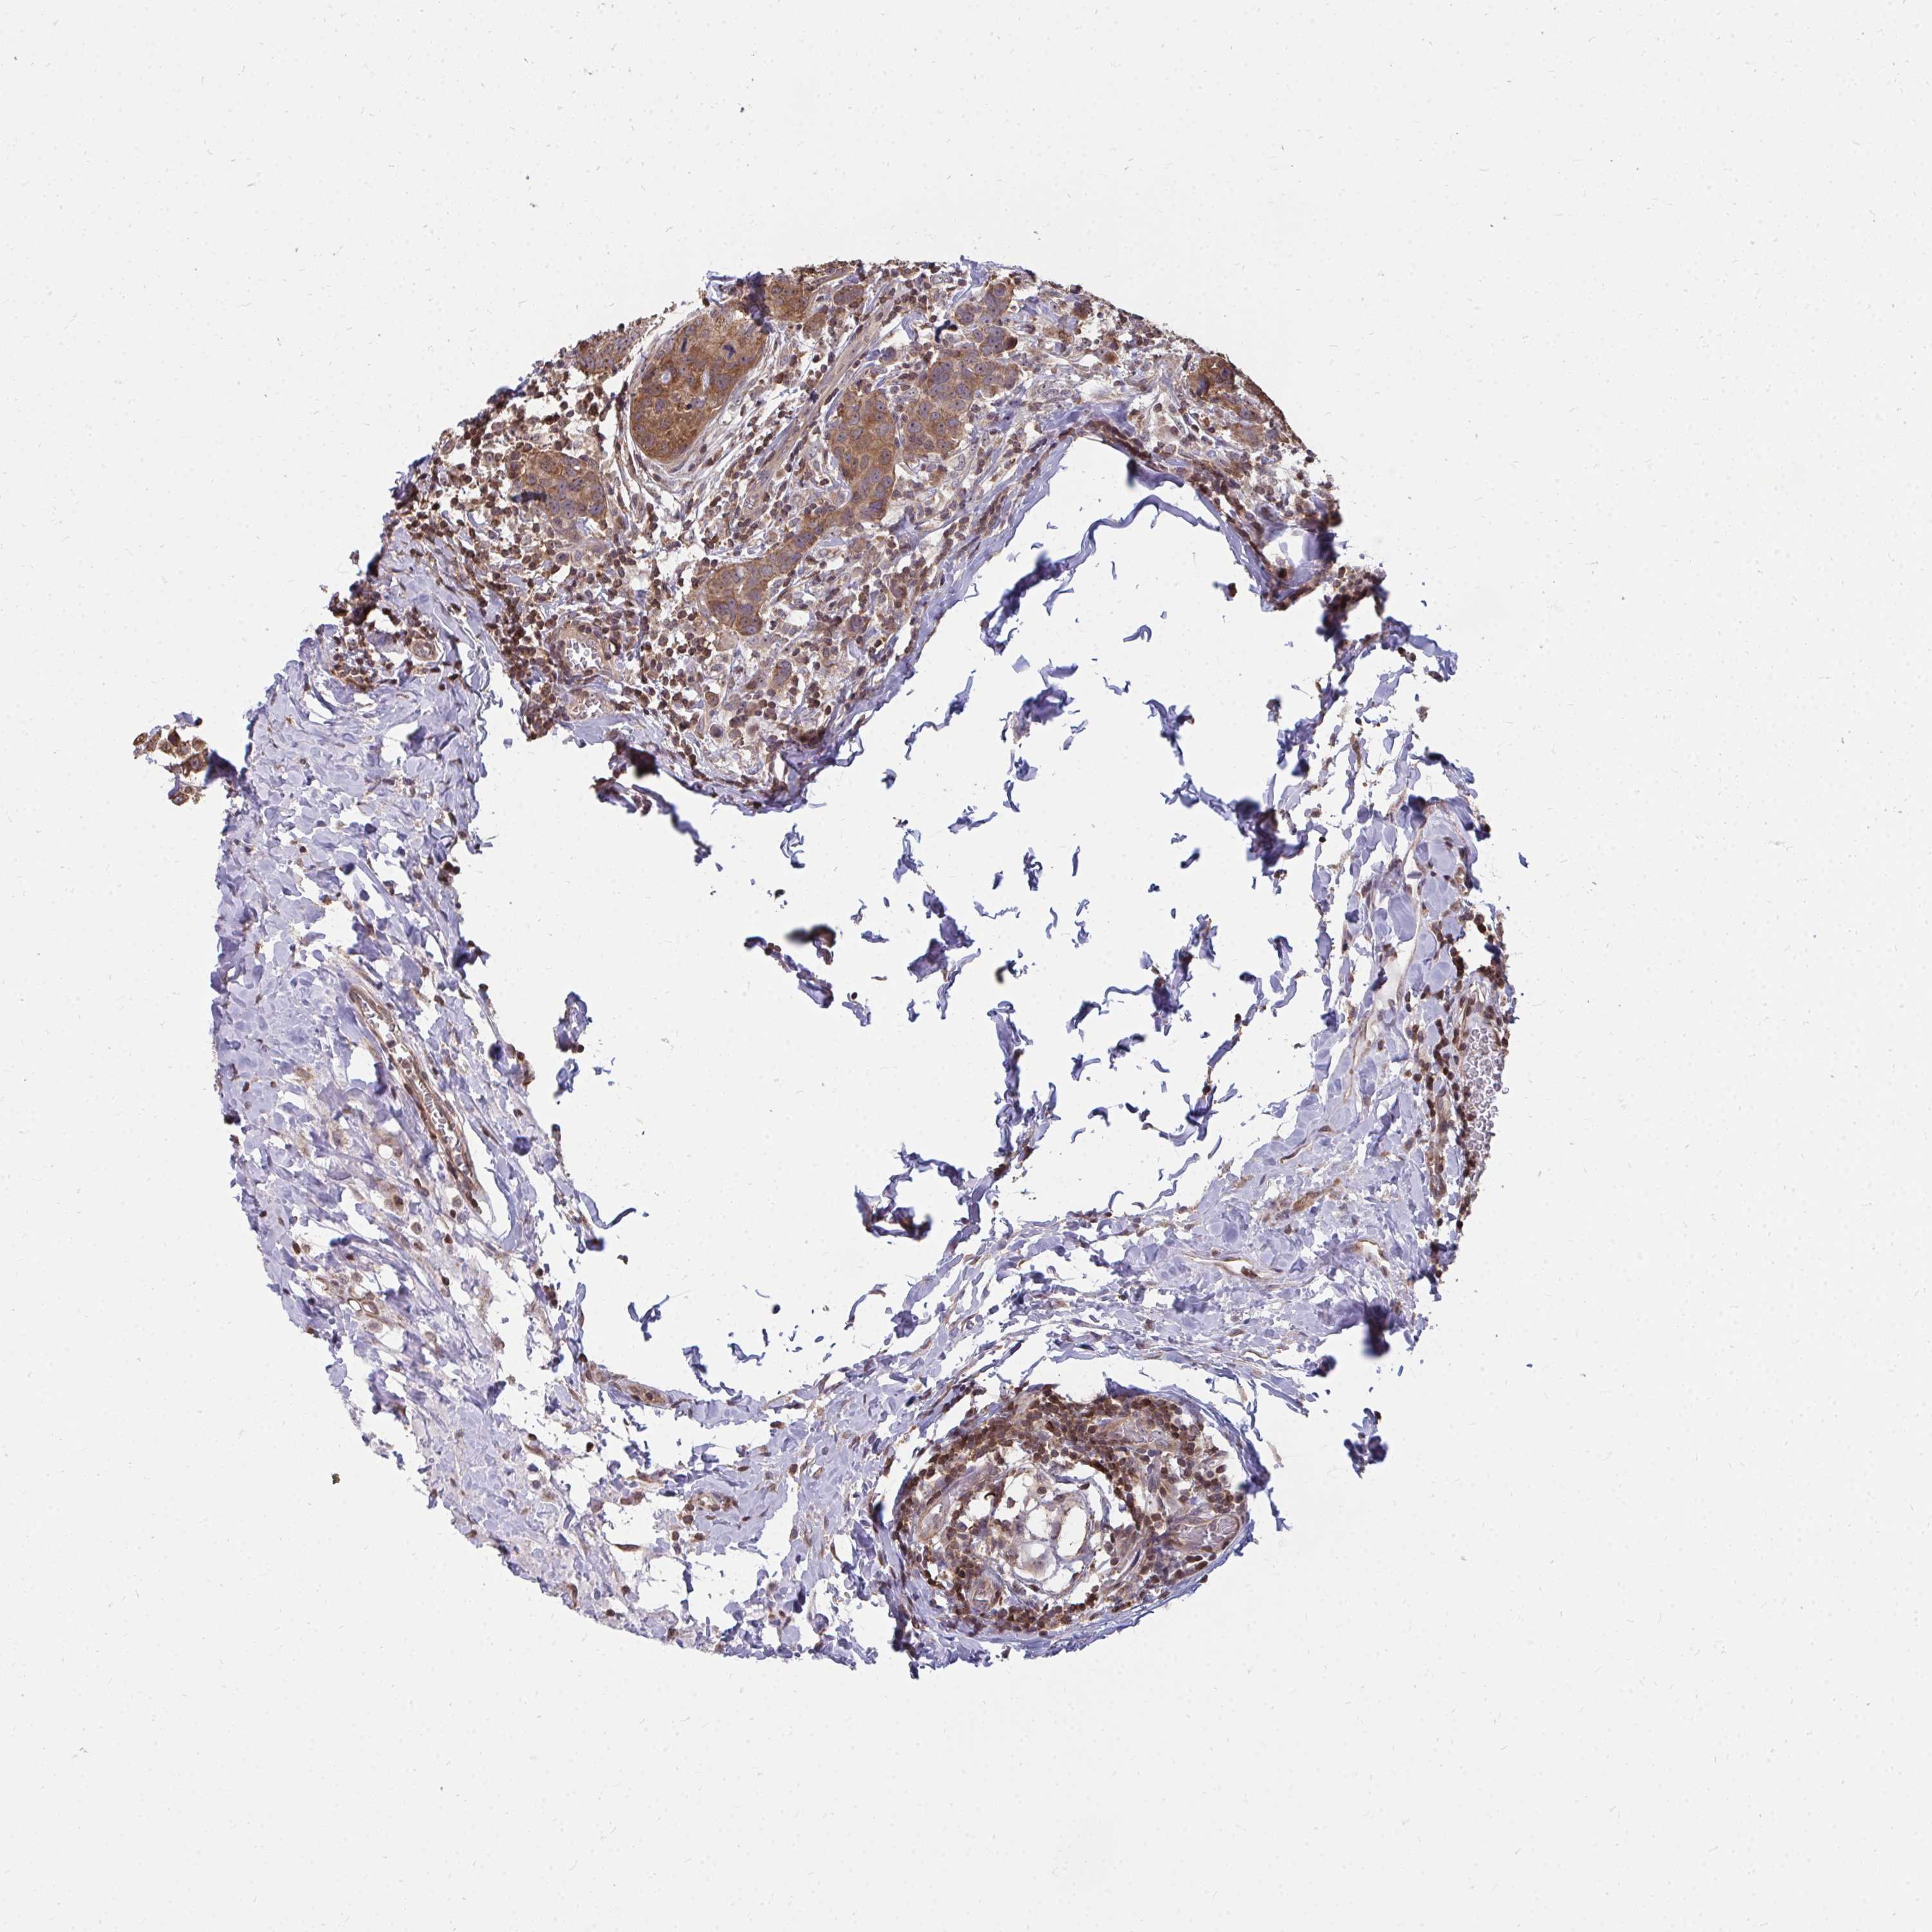

CANCER BREAST CANCER Show tissue menu

Breast cancer

Human cancer